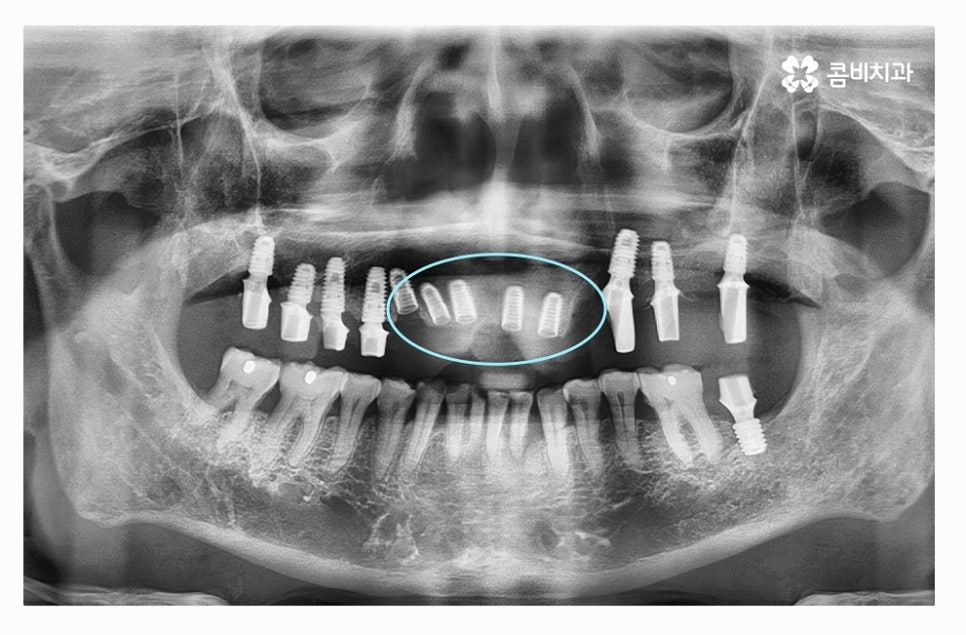

전체임플란트를 해야 할 때 주의사항은 잇몸을 최대한 보존하고

임플란트를 한꺼번에 식립해야 하기 때문에 3D CT 등을 활용한

정밀검진부터 철저하게 해야 하고 식립 각도 하나하나에

철저해야 하기 때문에 의료진의 경험과 실력이 중요한 시술이라 할 수 있어요.

만성치주염 환자분들의 경우 치아를 한꺼번에 발치한 후에

전체임플란트 치료 과정을 거치는 것 자체가

고난도의 시술이며 비용도 만만치 않지만